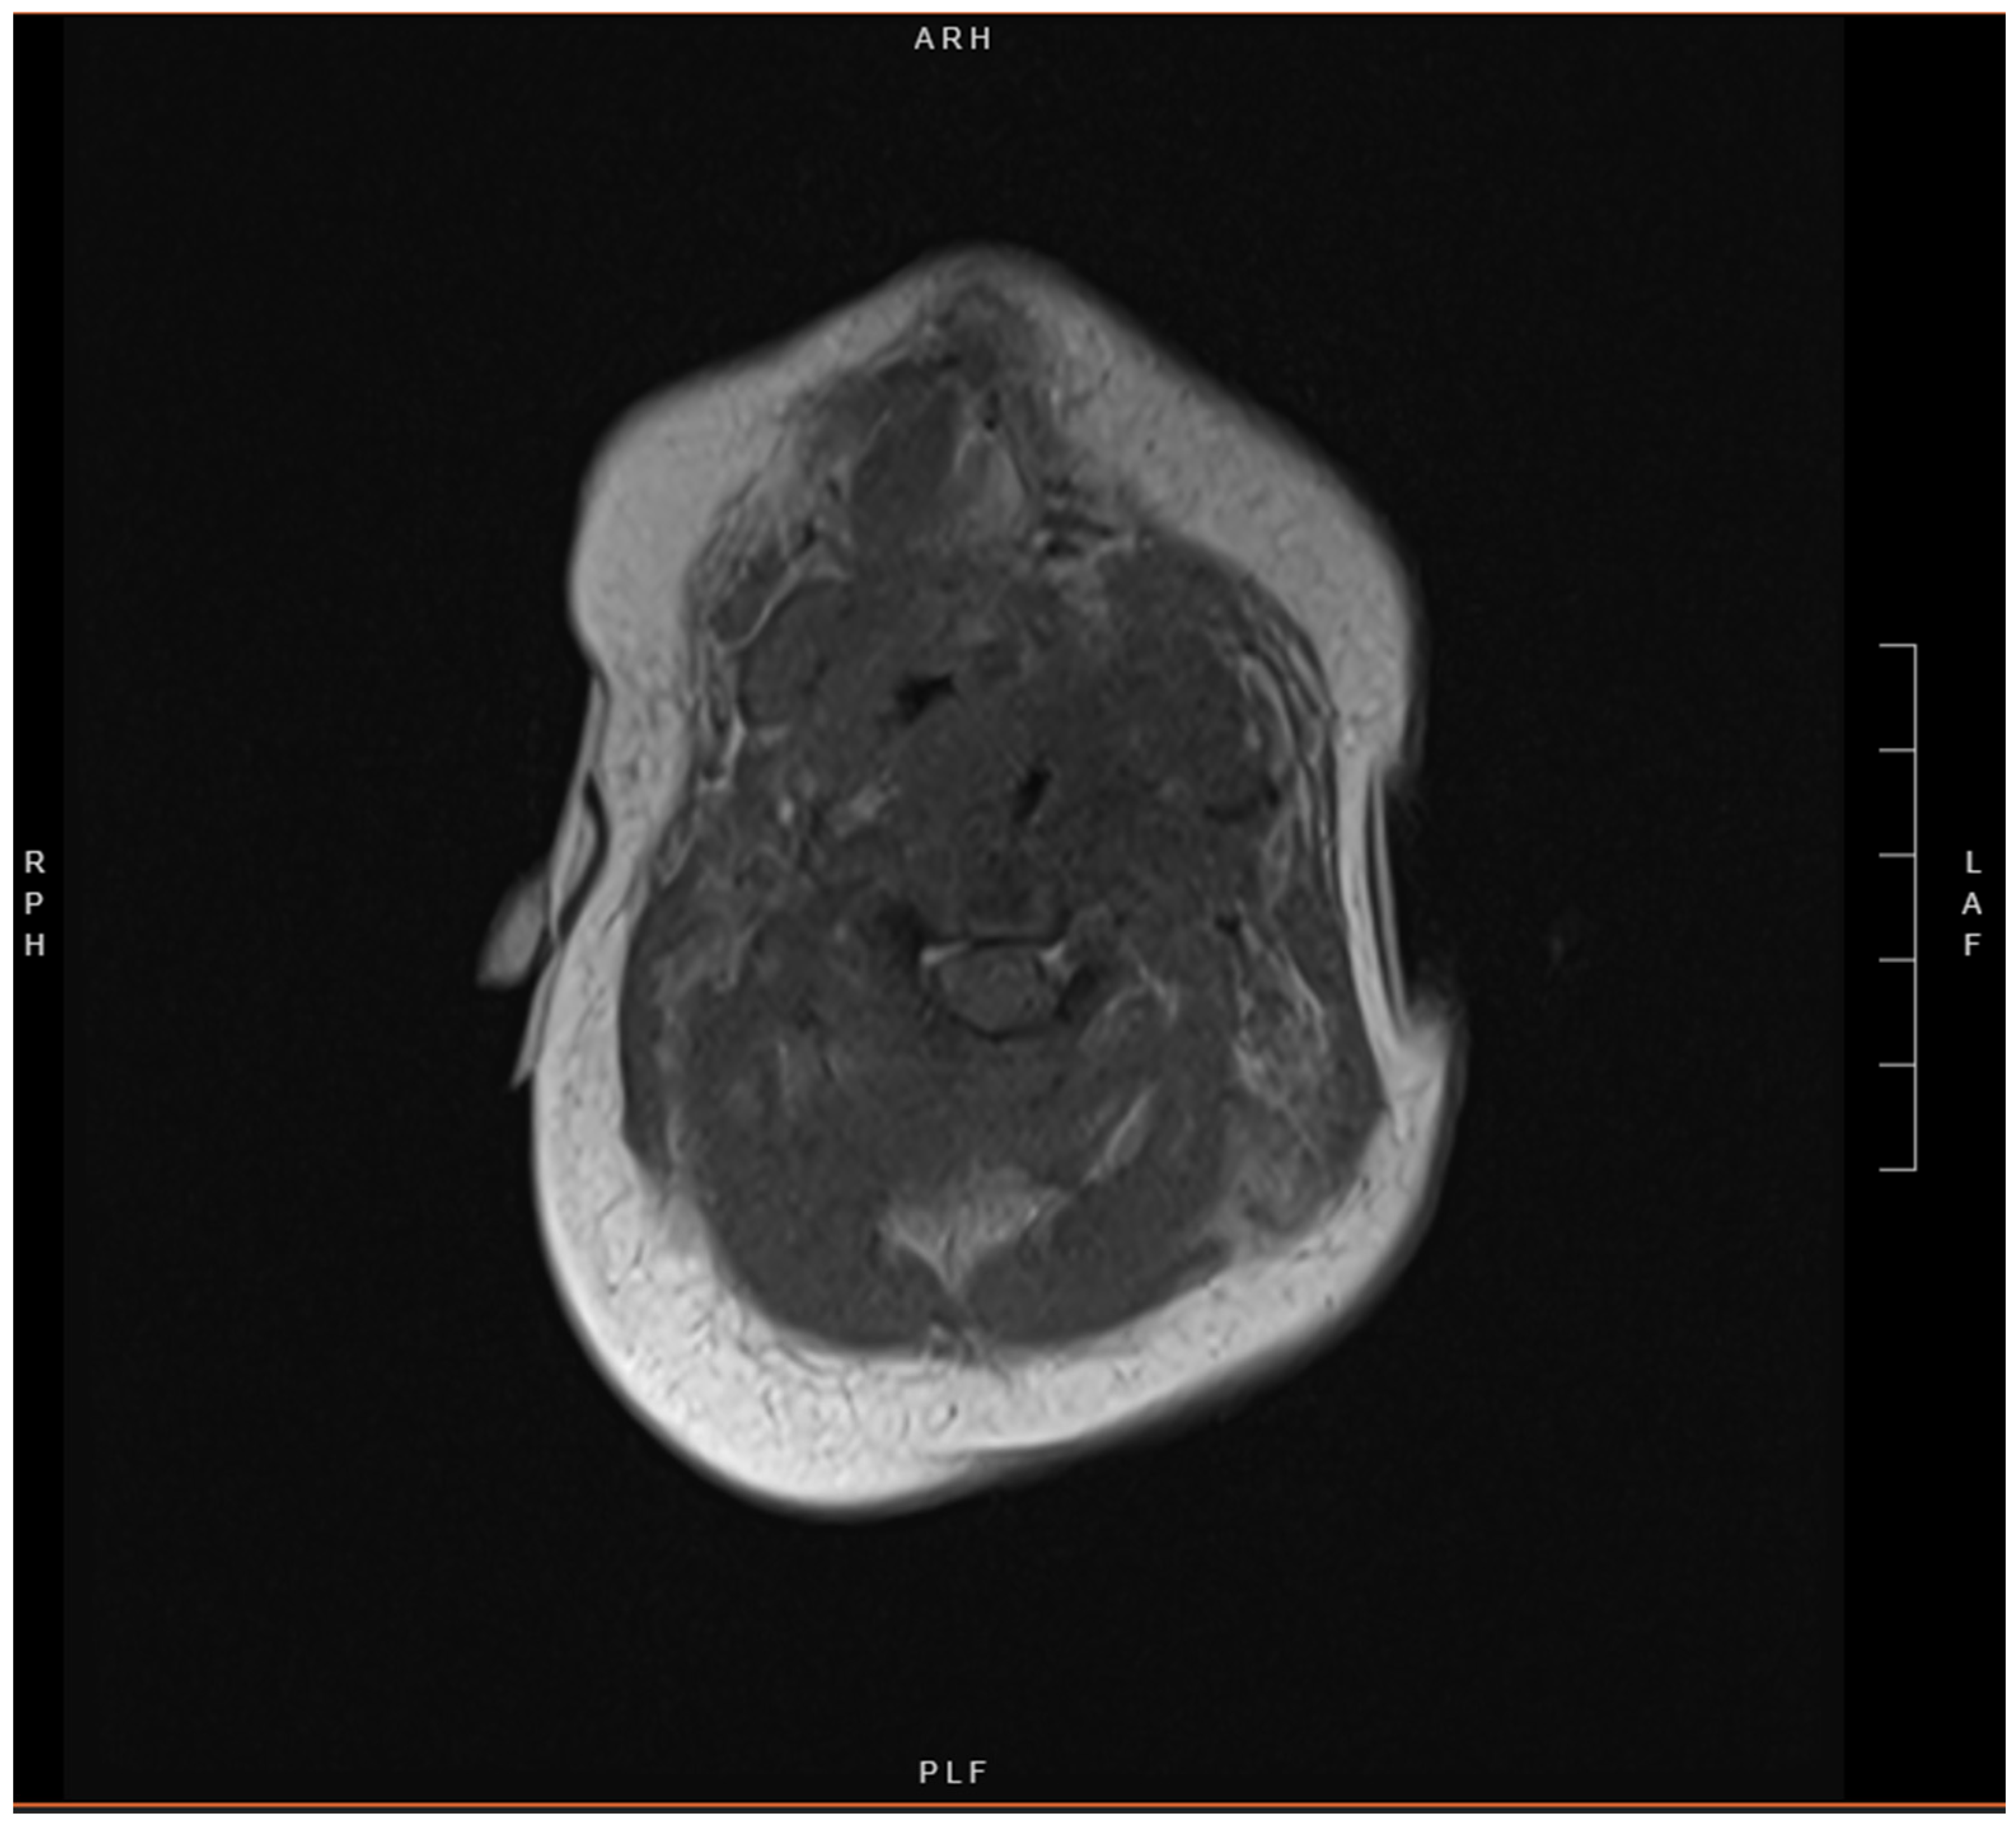

2. Case Presentation